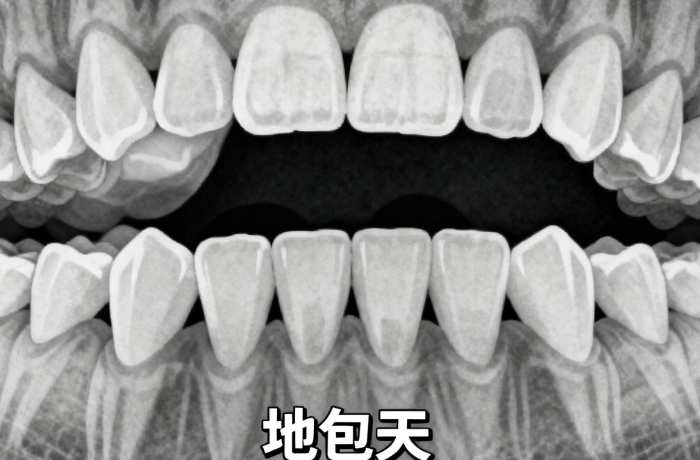

對于打算做正畸的普寧人來說,“不用咬惡心牙?!薄澳芴崆翱闯C正療效”是較在意的兩個核心訴求——畢竟傳統(tǒng)正畸的“咬牙?!边^程常讓人犯惡心,而“看不見較終療效”也容易讓人猶豫不前。ardc-srvc.com普寧健雅口腔醫(yī)院的正畸服務(wù)正好擊中了這些痛點,憑借“無牙模數(shù)字化流程”和“矯正療效可視化”的特色,成為不少患者的選擇。

傳統(tǒng)正畸的“咬牙?!绷鞒蹋呛芏嗳说摹靶睦黻幱啊薄岩粓F黏糊糊、有異味的硅橡膠塞進嘴里,需緊緊咬住5-10分鐘,咽反射敏感的人常忍不住干嘔,甚至吐出來。有患者分享:“之前在別家咬模,咬了三次才成功,每次都吐得眼淚直流?!倍⊙庞谩翱趦?nèi)掃描儀”替代了傳統(tǒng)牙模:掃描頭是光滑的塑料材質(zhì),醫(yī)生會先涂一層潤唇油減少摩擦,再緩慢在口腔內(nèi)移動掃描,整個過程僅5-8分鐘,沒有異物感,也沒有異味。

掃完后,電腦立刻生成1:1的牙齒3D模型,患者能當(dāng)場看到自己牙齒的每一處細節(jié),比如“虎牙的傾斜角度”“牙縫的大小”。有患者說:“掃的時候像用棉花簽輕碰牙齒,全程沒難受,反而覺得新鮮。”